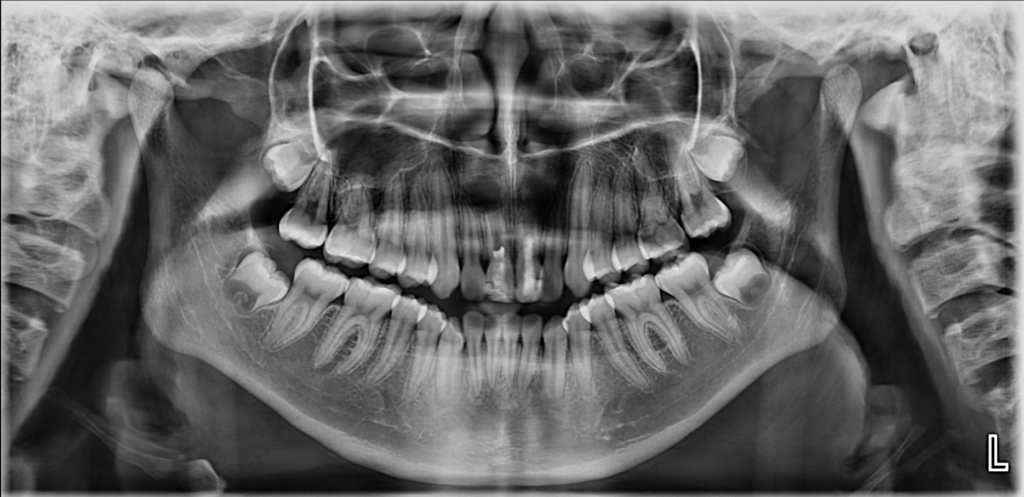

En la radiografía panorámica (Figura 1) se observan las piezas 11 y 21 con disminución de la longitud radicular, conductos radiculares amplios y ápices abiertos. Asimismo, se evidencia material restaurador coronario desadaptado, obturación endodóntica parcial y la presencia de un proceso osteolítico periapical difuso.

RADIOGRAFÍA PANORÁMICA